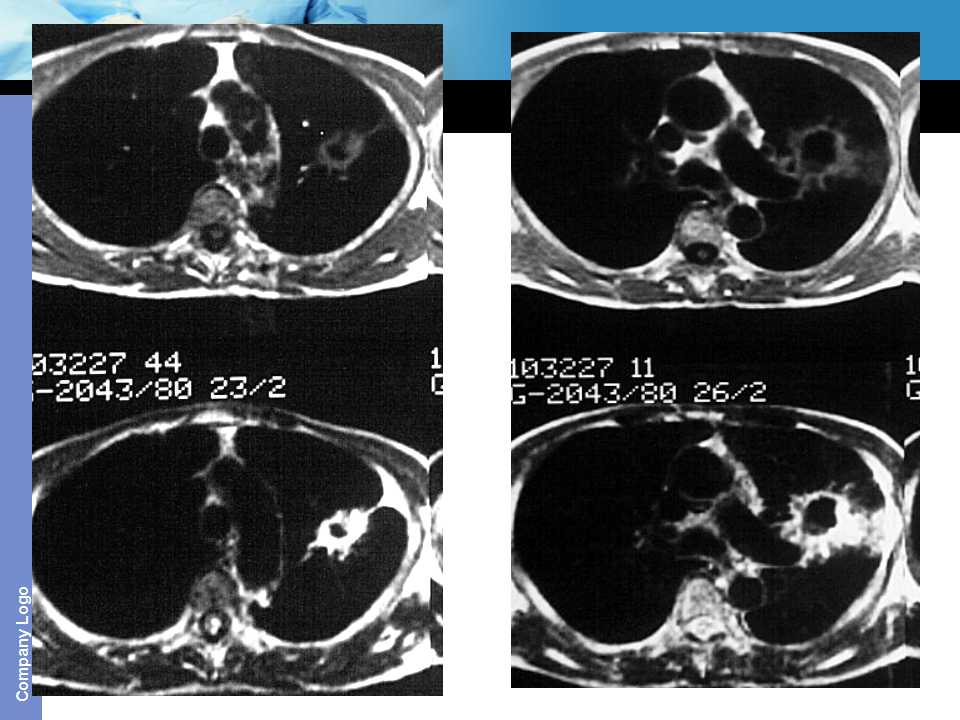

肺癌影像诊断